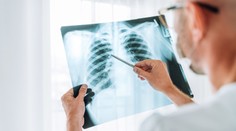

Pľúca Porovnanie snímok pľúc je šokujúce: Po-covidové sú oveľa horšie ako pľúca tuhých fajčiarov Jana Habarová 17. 1. 2021